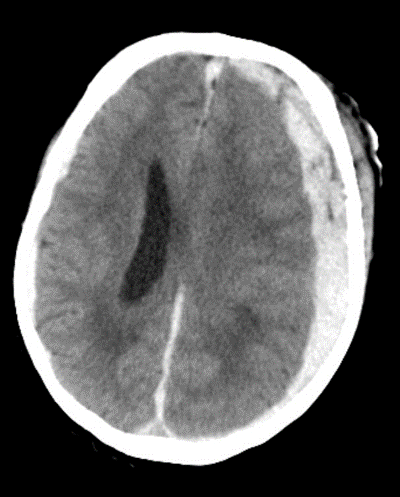

Diagnosis?

Subdural Hemorrage